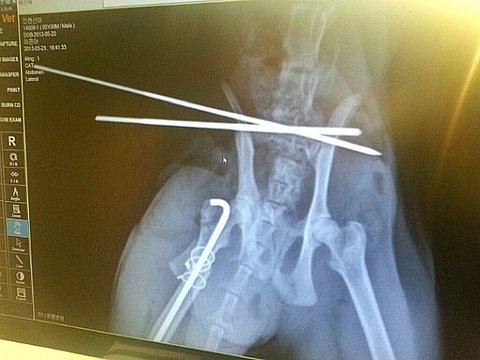

골반골절/대퇴골절 수술후 일주일 사진주의 [신이]

대퇴골절, 골반골절, 안락사 판정... 교통사고로 제게 온 길고양이... 신이...

교통사고를 당해 대퇴부 및 골반골절로 안락사 판정을 받았고 주인 없는 길고양이 신이가

할수 있는건 아무것도 없었어요. 수술이 잘된다해도 배변장애와 후지마비의 가능성 또한

선생님들의 긴 회의끝에 병원에선 신이를 수술해서 살리기로 결정하였고 그렇게 네달의 긴 입원기간...

'수술후 신이의 모습은 정말 처참하고 안쓰러워 눈물밖에 안나왔습니다.